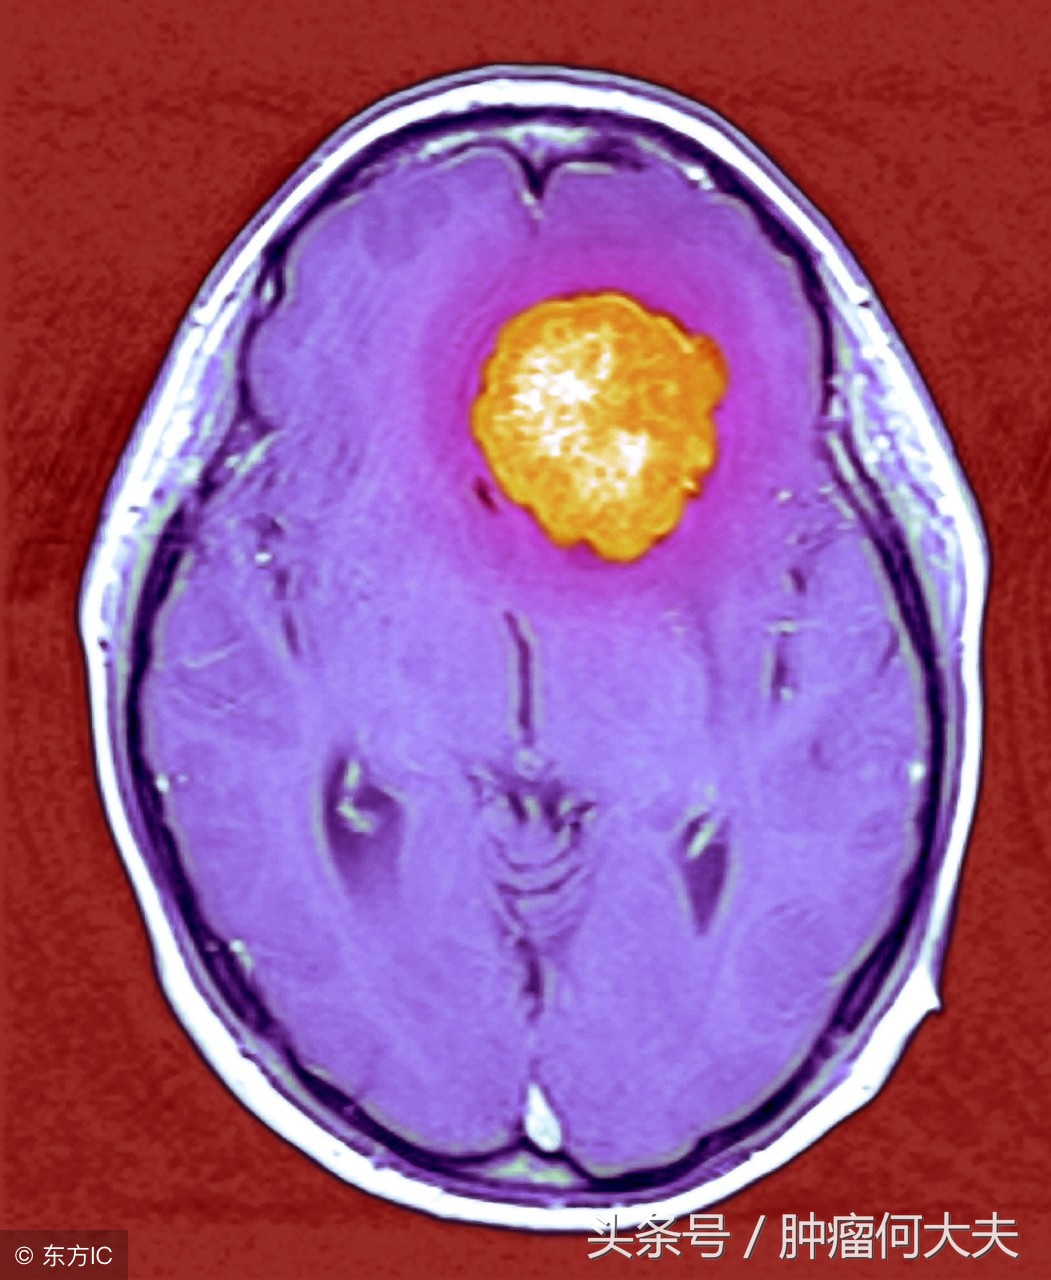

怀疑脑膜瘤要做哪些检查? 头颅CT及MRI增强检查:能提供肿瘤大小、部位、能否手术等重要信息。脑膜MRI特点是显示肿瘤均一强化,有硬膜尾征,有皮质扣压征,有假包膜形成,瘤周水肿,骨质破坏;脑血管造影检查:可见肿瘤染色,供血动脉增粗,颈动脉血循环增快;PET-CT检查:对了解病变浸润范围及有无术后残留和复发有重要的参考价值。患者有上述临床表现并有影像学表现之一者即可临床诊断脑膜瘤。确诊及病理分类依靠术后病理组织学检查。